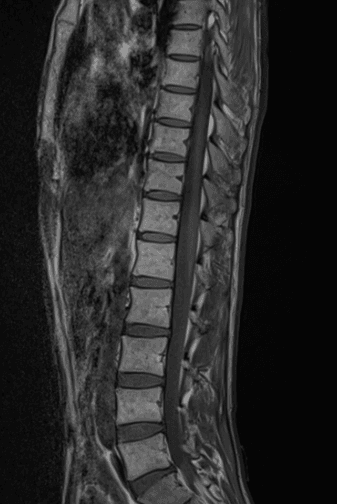

이런 경우에 골절이 아닌지 오해하시는 경우가 많은데 골절이 아닙니다.

골절의 경우에는 T1 영상에서 조영이 떨어지고 fat suppression T2 영상에서 조영이 증가하는 소견을 확인해야합니다.

골절이 아니면 왜 저렇게 보이는지 까지는 제가 잘 모르지만 저 소견을 이상소견으로 보이는 않습니다.